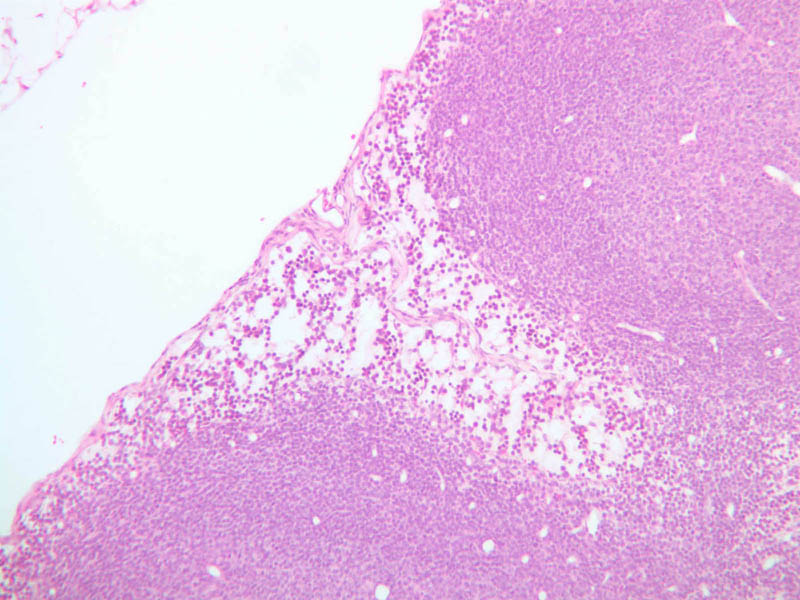

The first site of defense against foreign agents entering the body through the mouth and nose is the ring of tonsils around the posterior oro- and nasopharynx. The tonsil is a mass of confluent lymphoid nodules beneath the pharyngeal epithelium. Examine slide A-41 (retic-H&E [2.5x, 2.5x-labeled] [2.5x, 10x-labeled, 20x, 40x] [2.5xlabeled, 10x, 20x, 40x]). Tonsillar tissue is not separable into cortical and medullary regions, and it does not contain lymphatic vessels. The lymphoid masses, as in the nodules of the stomach and intestine, lie just beneath the epithelium where they can intercept bacteria and viruses that either invade or are phagocytosed by the overlying epithelium. The tonsil is invested by a fibrous tissue and is incompletely subdivided by inward-projecting trabeculae. Blood vessels in the tonsillar substance leave randomly through the fibrous tissue. What features differentiate the tonsil from the ileum?

A41, Tonsil, 2.5x (Reticulin-H&E) A41, Tonsil, 2.5x Labeled (Reticulin-H&E) A41, Tonsil, 2.5x (Reticulin-H&E) A41, Tonsil, 10x Labeled (Reticulin-H&E) A41, Tonsil, 20x (Reticulin-H&E) A41, Tonsil, 40x (Reticulin-H&E) A41, Tonsil, 2.5x Labeled (Reticulin-H&E) A41, Tonsil, 10x (Reticulin-H&E) A41, Tonsil, 20x (Reticulin-H&E) A41, Tonsil, 40x (Reticulin-H&E)